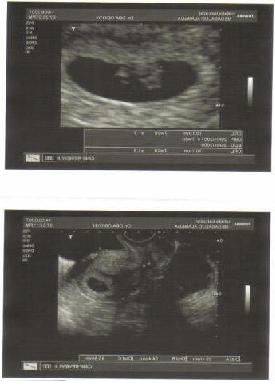

Y un nuevo amor crece en mi pecho inmigrante;

Al mismo tiempo que tus células de zigoto

se multiplican, y se multiplican, y se vuelven a multiplicar....